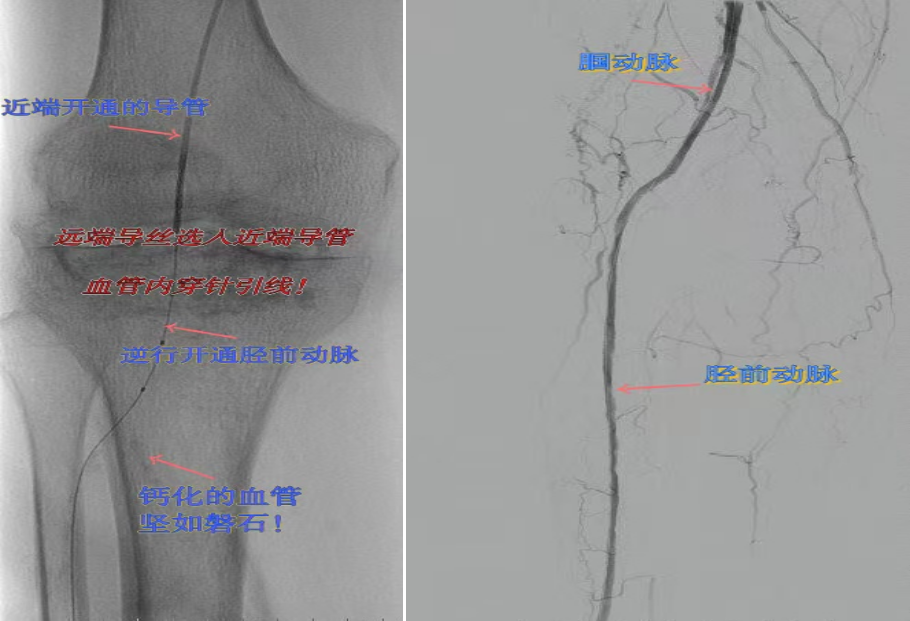

67岁女性患者,多年糖尿病、冠心病史,因右足溃烂伴凉麻疼痛长达2年就诊,此前曾接受外院介入术后血管再度闭塞。此次检查发现其股浅动脉、腘动脉至膝下血管全程闭塞,且伴有严重钙化。团队迎难而上,创新性经足背动脉逆向穿刺,耗时3小时成功贯通胫前动脉。术后当夜患者足部即感回暖,溃烂足趾疼痛显著缓解。术后结合中药外治(换药、熏洗、去腐生肌膏外敷)加速创面愈合。该患者已于出院,院外换药治疗。

影像检查:股浅动脉、腘动脉至膝下血管全程闭塞伴严重钙化。